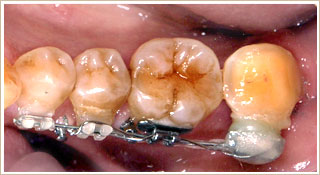

3ヶ月後です。移動距離の半分ぐらい動いてきました。

傾斜していた歯も起きあがり、終了間近です。

装置をはずして、1年後です。問題なく噛める状態が維持されています。